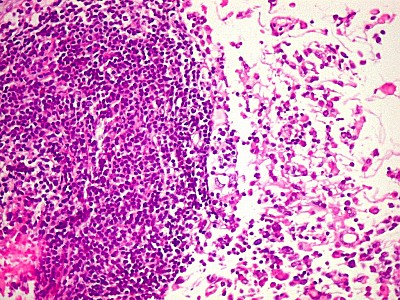

| GFAP.

Positivo no tumor, negativo no folículo linfóide. Indica

expressão do filamento intermediário próprio de astrócitos. |